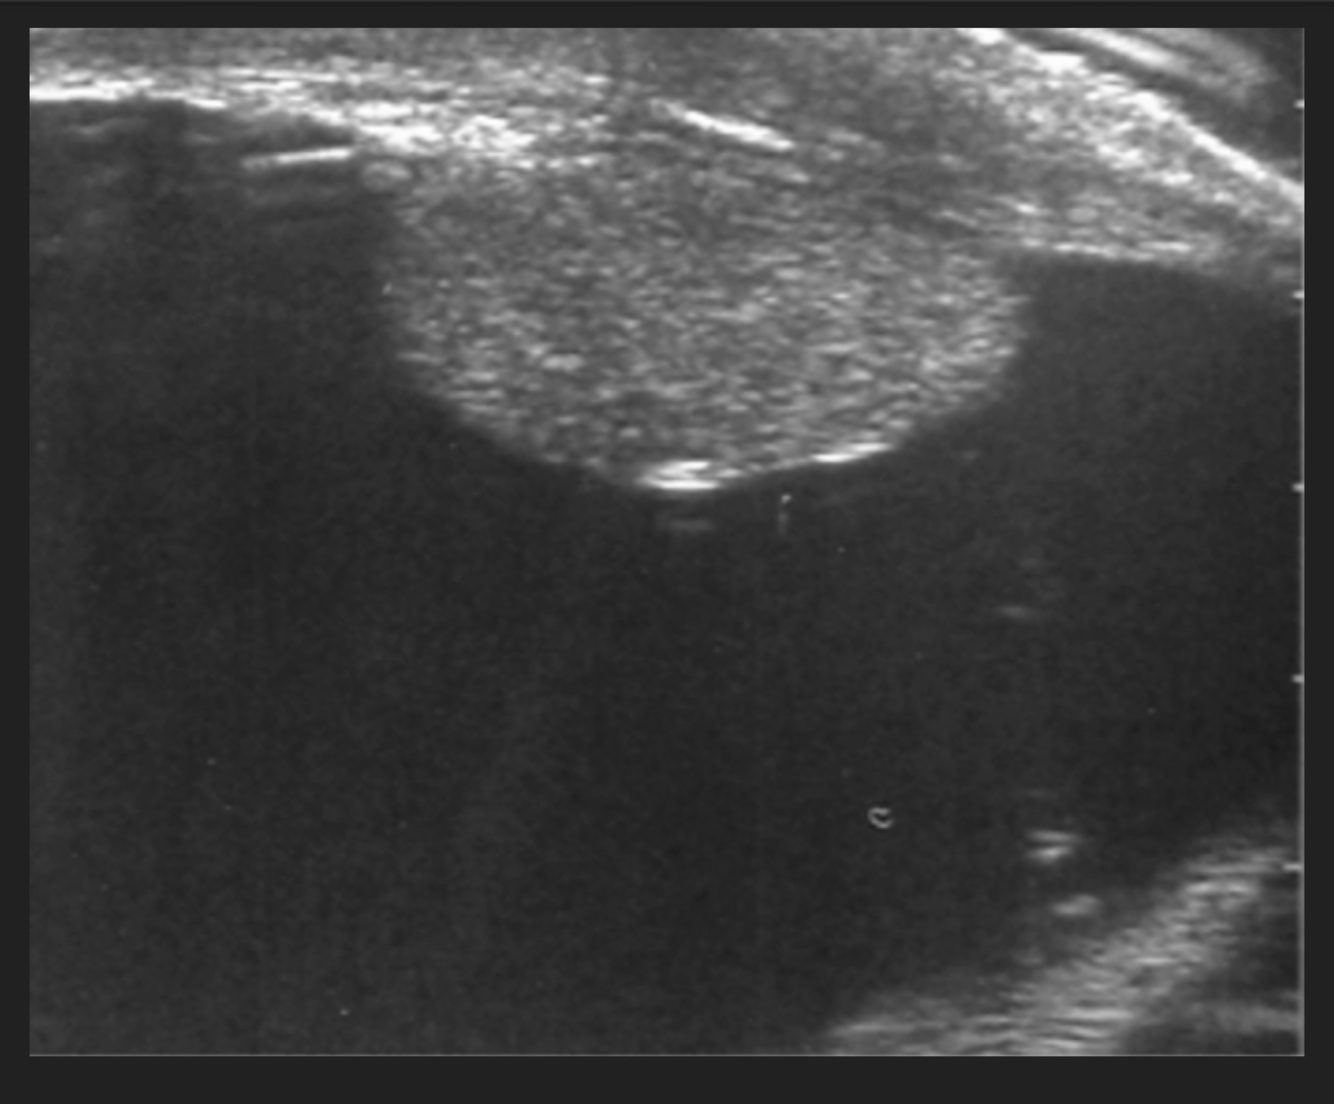

4

Q

Masculino de 56 años, olor y aumento de volumen testicular, imagen de USG

A

Hidrocele